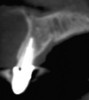

Fig 8. Case 1: A patient presented in January 2006 with a large periapical lesion, a root fracture, and significant buccal bone loss.

Figure 8

Fig 9. Despite the extent of bone loss revealed radiographically, multiple surgical grafting procedures were not indicated. Instead, a flapless surgery would be performed and biologic innovations used to facilitate ridge preservation.

Figure 9

A patient presented with a large periapical lesion, root fracture, and significant loss of buccal bone (Figure 8 and Figure 9). Treatment for this case involved an autogenous bone graft, then implant placement and connective tissue grafting. Recombinant human platelet-derived growth factor-BB was used for ridge preservation and minimally invasive esthetic implant site development with a flapless approach.